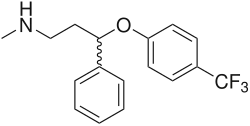

Selective norepinephrine reuptake inhibitors

Norepinephrine–dopamine reuptake inhibitors (NDRIs)

Serotonin–norepinephrine reuptake inhibitors (SNRIs)